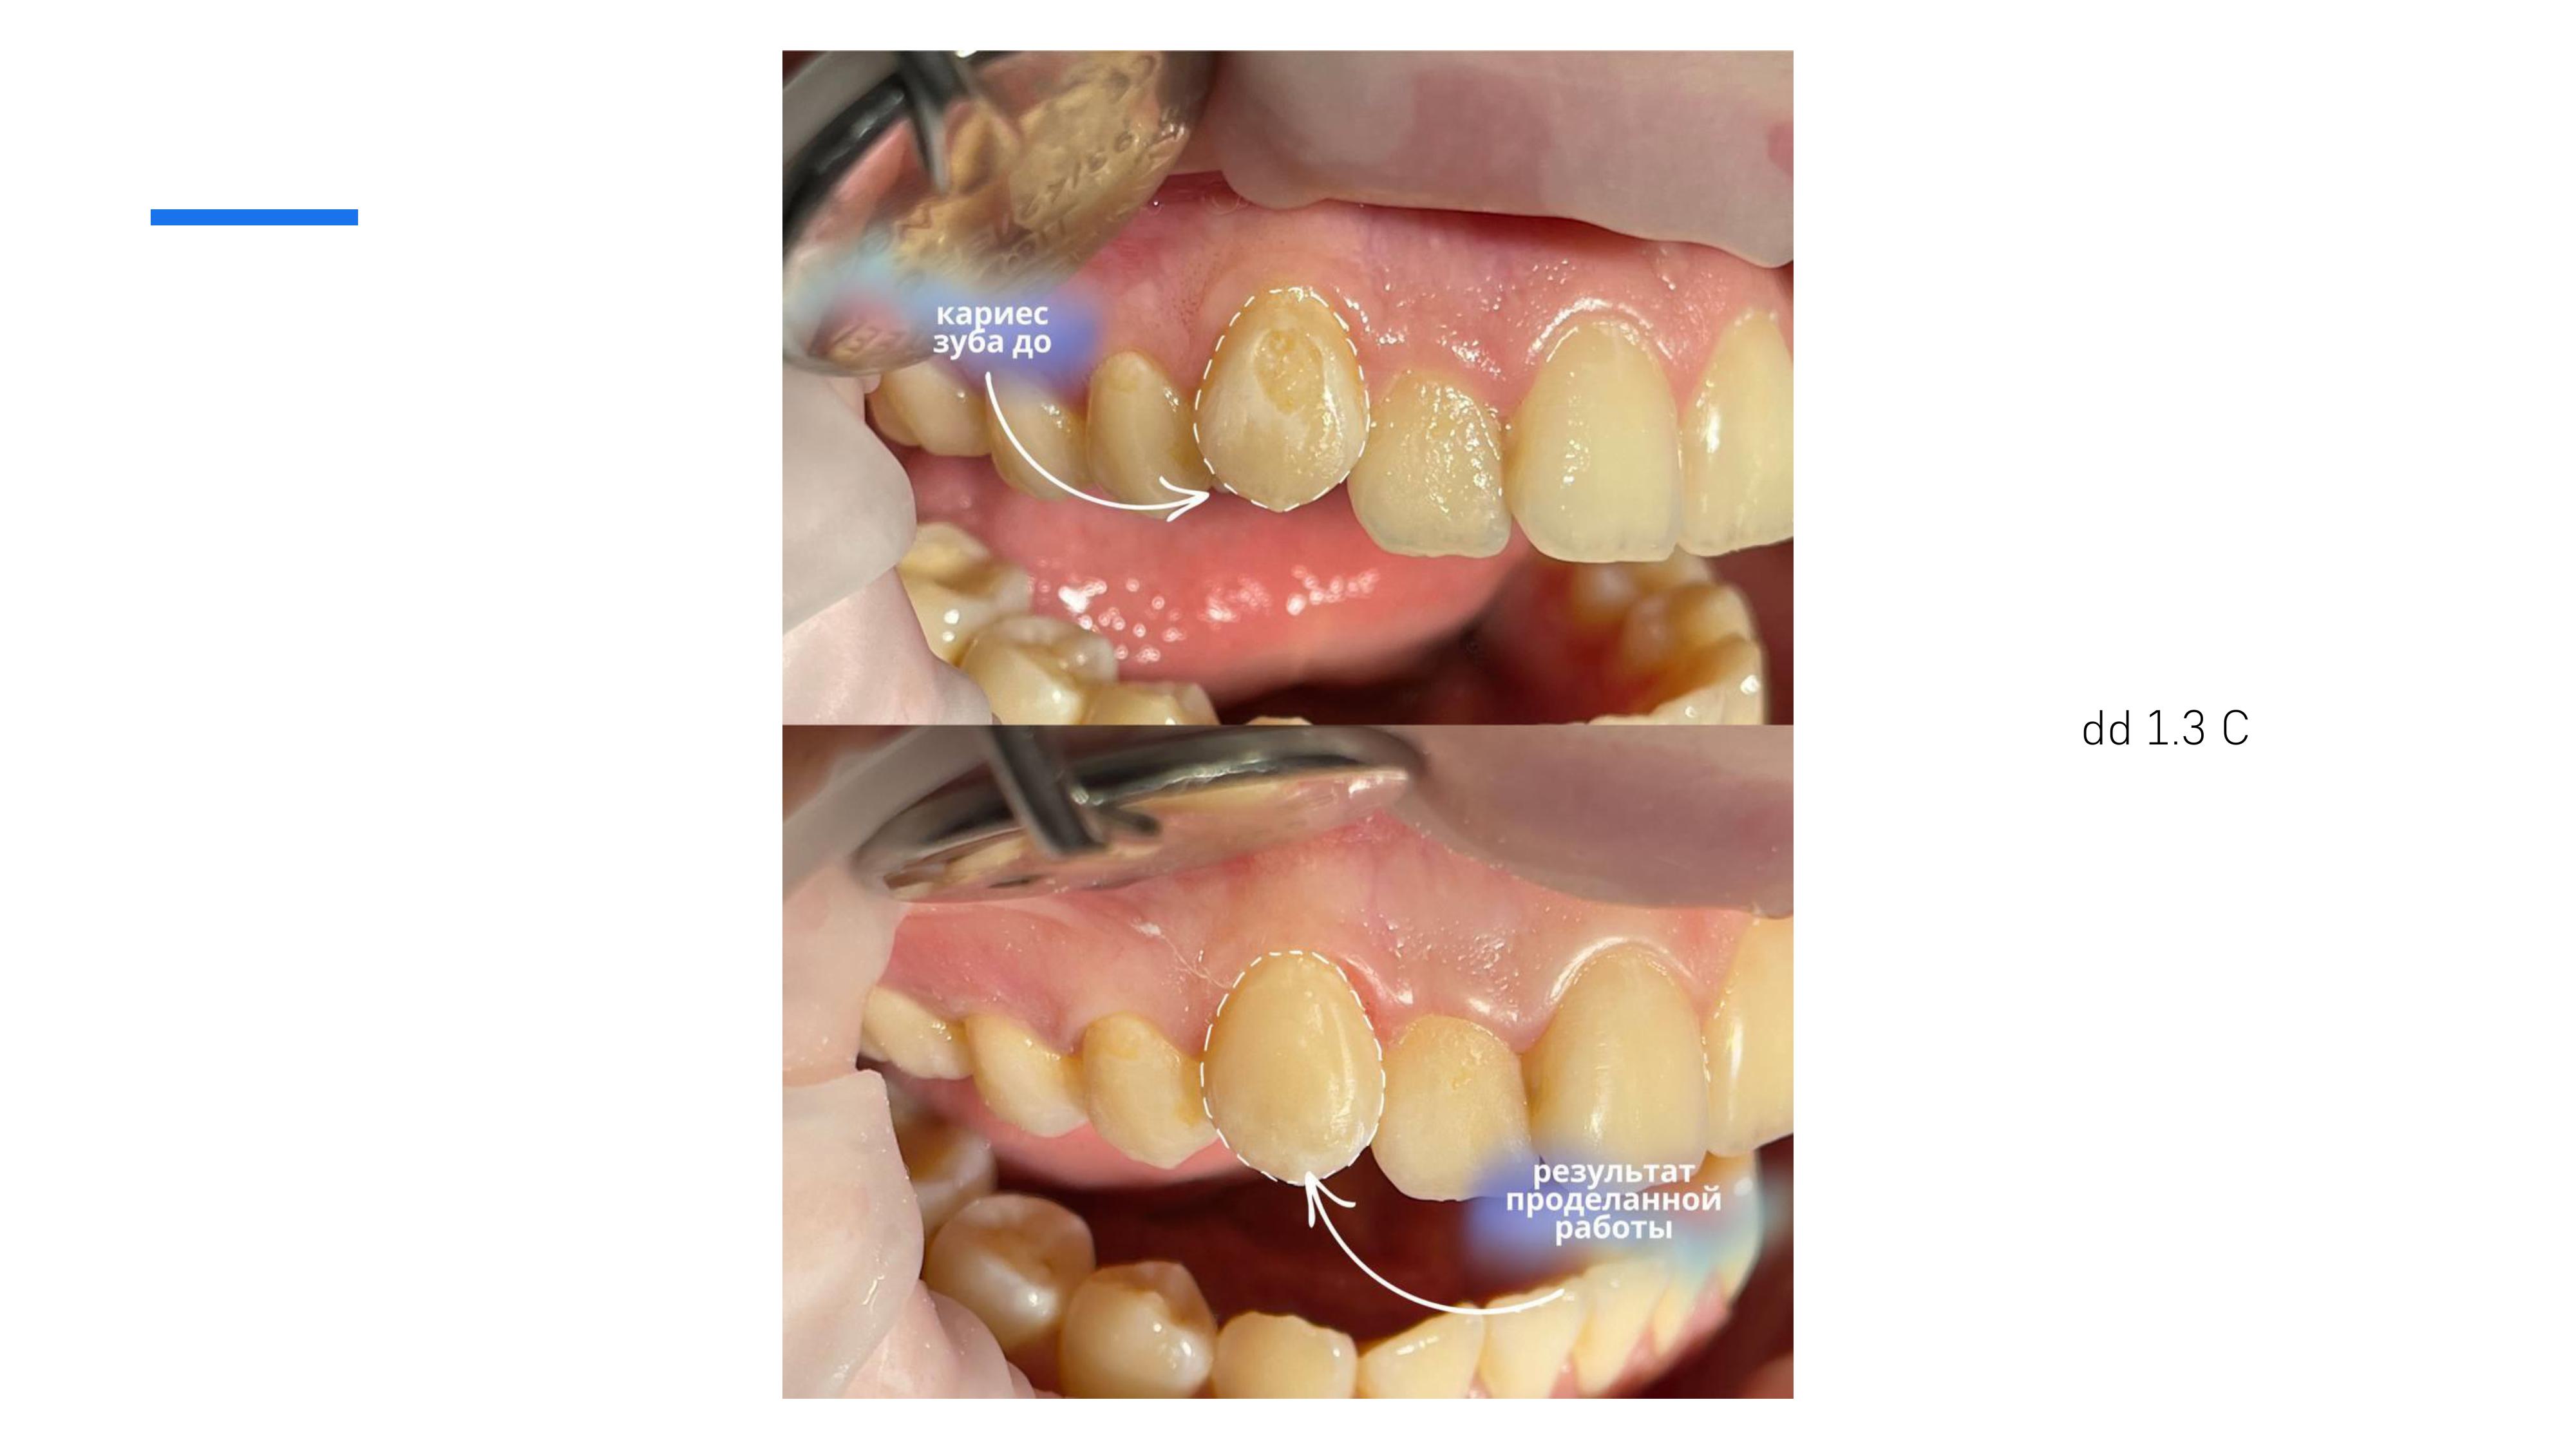

5. Художественная реставрация всех групп зубов современными пломбировочными материалами, эстетическая реставрация зубов.

6. Диагностика и лечение кариеса временных и постоянных зубов с использованием микроскопа, лечение пульпитов и периодонтитов временных и постоянных зубов.